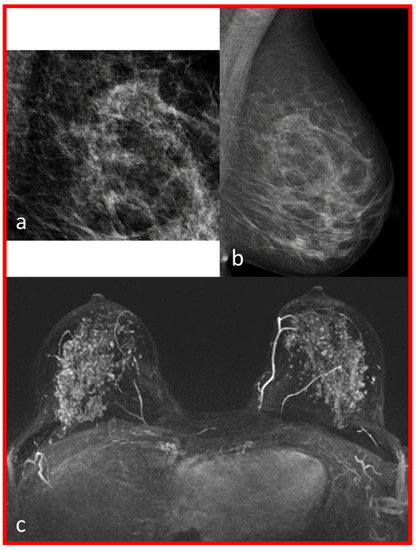

| 1 | 2 | Moderate | B | Intermediate-grade DCIS (6.5 cm) | No contrast enhancement in the position of macrocalcifications, multiple small foci on both sides. |